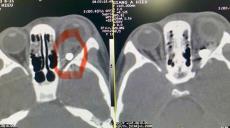

Báo động trò chơi súng ná cao su bắn bi sắt gây mù mắt

Bệnh viện Mắt Trung ương vừa tiếp nhận một trường hợp bệnh nhi 9 tuổi tên là Giàng A Hiếu (dân tộc H’Mông, xã Chiềng Cang, huyện Sông Mã, tỉnh Sơn La) trong tình trạng mắt trái bị rách góc mi trong, thị lực sáng tối âm tính, đặc biệt qua kết quả chụp chiếu phát hiện có dị vật hình tròn trong hốc mắt kích thước khoảng 3-4mm, nghi là viên bi sắt.